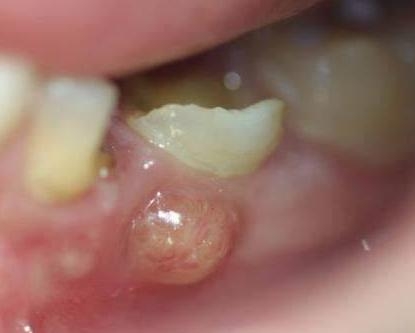

根尖周炎导致的牙龈“鼓包”

根尖片上显示严重的根尖周炎,可能导致牙齿无法保留